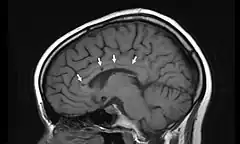

![]() Vista lateral de una resonancia magnética nuclear de la cabeza. Las flechas indican la localización de microinfartos cerebrales característicos del síndrome de Susac. | ||

El síndrome de Susac en una rara enfermedad descrita en 1979 por el neurólogo norteamericano John Susac. Es una microangiopatía que provoca la oclusión de los pequeños vasos sanguíneos que aportan sangre al cerebro, la retina y el oído interno. Técnicamente se describe como una microangiopatía que afecta a las arteriolas precapilares. Los síntomas principales son dolor de cabeza, déficit cognitivo, pérdida de memoria, dificultad para la marcha, pérdida de visión y disminución de la capacidad auditiva (hipoacusia). La causa es desconocida, pero se cree que está provocado por un fenómeno de autoinmunidad. El tratamiento se basa en la administración de agentes inmunosupresores que disminuyen la respuesta inmunitaria, entre ellos glucocorticoides, azatioprina y metotrexate.[1][2][3][4]